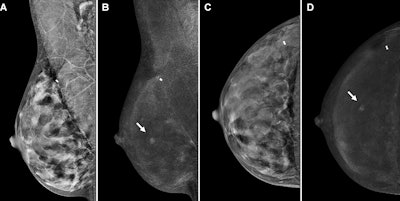

Contrast-enhanced mammography (CEM) images depict a 56-year-old woman with a history of atypical ductal hyperplasia show cancer. Images include the following: screening (A, B) mediolateral oblique views and (C, D) craniocaudal views on (A, C) low-energy images and on (B, D) recombined images in the right breast. At the central slightly outer area in the right breast, mid-depth, there is a new enhancing mass (arrows) with no correlate on low-energy images. Subsequent targeted ultrasound showed a 0.5-cm irregular hypoechoic mass (not shown) for which ultrasound-guided biopsy showed invasive carcinoma, with a 1.2-mm invasive component at surgical pathologic examination and with negative nodes. Image courtesy of the RSNA.